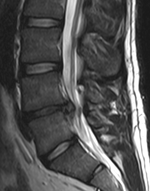

التشخيص الكامل عادة من خلال مزيج من التاريخ الطبي للمريض، والفحص البدني، وعند الاقتضاء، الاختبارات التشخيصية، مثل أشعة الرنين المغناطيسي أو الأشعة السينية.